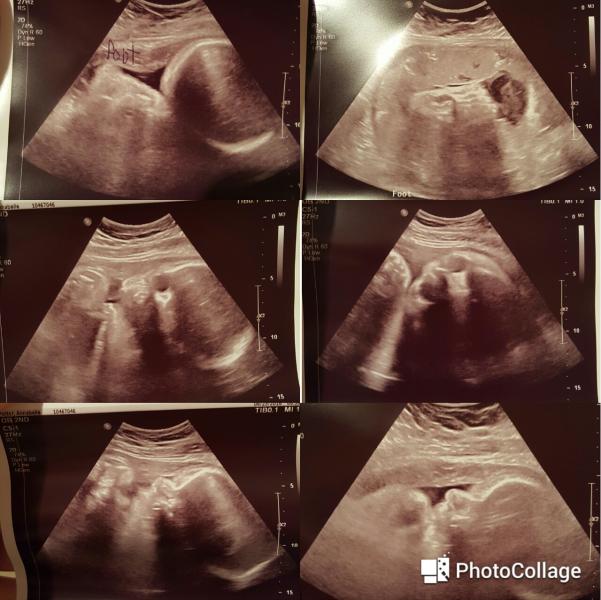

We got to see our babygirl this morning.

Feet pics at the top. The rest are profile and face pics. I never thought Id get a creepy face pic, lol. But the more I look at it the more I can actually see her and see how beautiful she is going to be.

They said shes about 5lbs 15ozs, and in the 48th percentile, shes right on track.